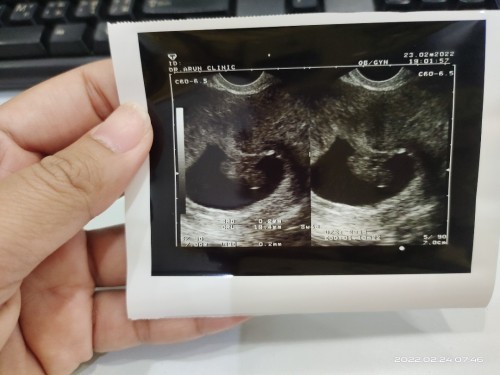

ของเราพึ่งหลุด ออกเองสมบูรณ์ แบบนี้เลย ซาวด์4รอบหมอบอกทำใจ เสียใจมาก

หมอให้รอ 5 วันคะ แล้วซาวอีกรอบ ถ้าไม่เจอต้องขูดมดลูก เอาน้องออกคะ😭